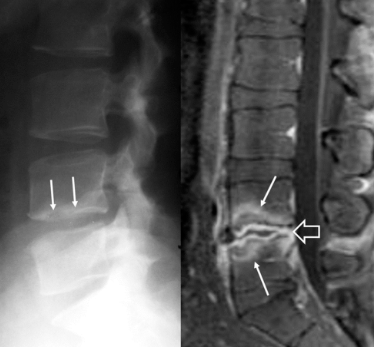

Initial lateral radiograph (left) shows a cortical disruption at the inferior epiphyseal plate of L4 vertebral body (arrows). The sagittal fat suppressed contrast enhanced T1-w MR image (right) shows septic discitis (open arrow) and bone marrow edema on both L4 and L5 vertebral bodies (arrows), suggesting spondylitis.

• Chief complaint: 34 year-old farmer from Sicily presents with worsening back pain after sitting for more than couple of hours

• No other significant past medical history